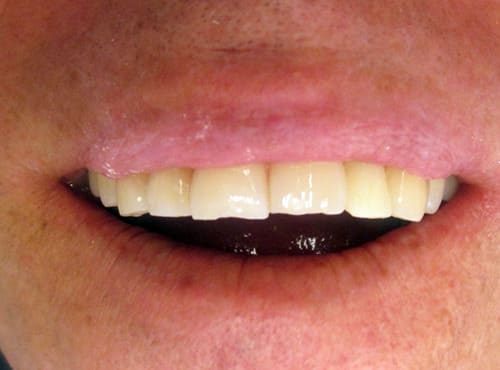

J'ai le plaisir de vous présenter un cas clinique de couronne E-Max sur 22 réalisé à partir de l'empreinte optique intra-buccale.

sur la photo "maquillage" on voit que le bord du provisoire a été un peu envahissant sur la canine, avec le bridge définitif la gencive est revenu a sa place, avec des bords foireux la gencive ne revient pas

Joli bridge.